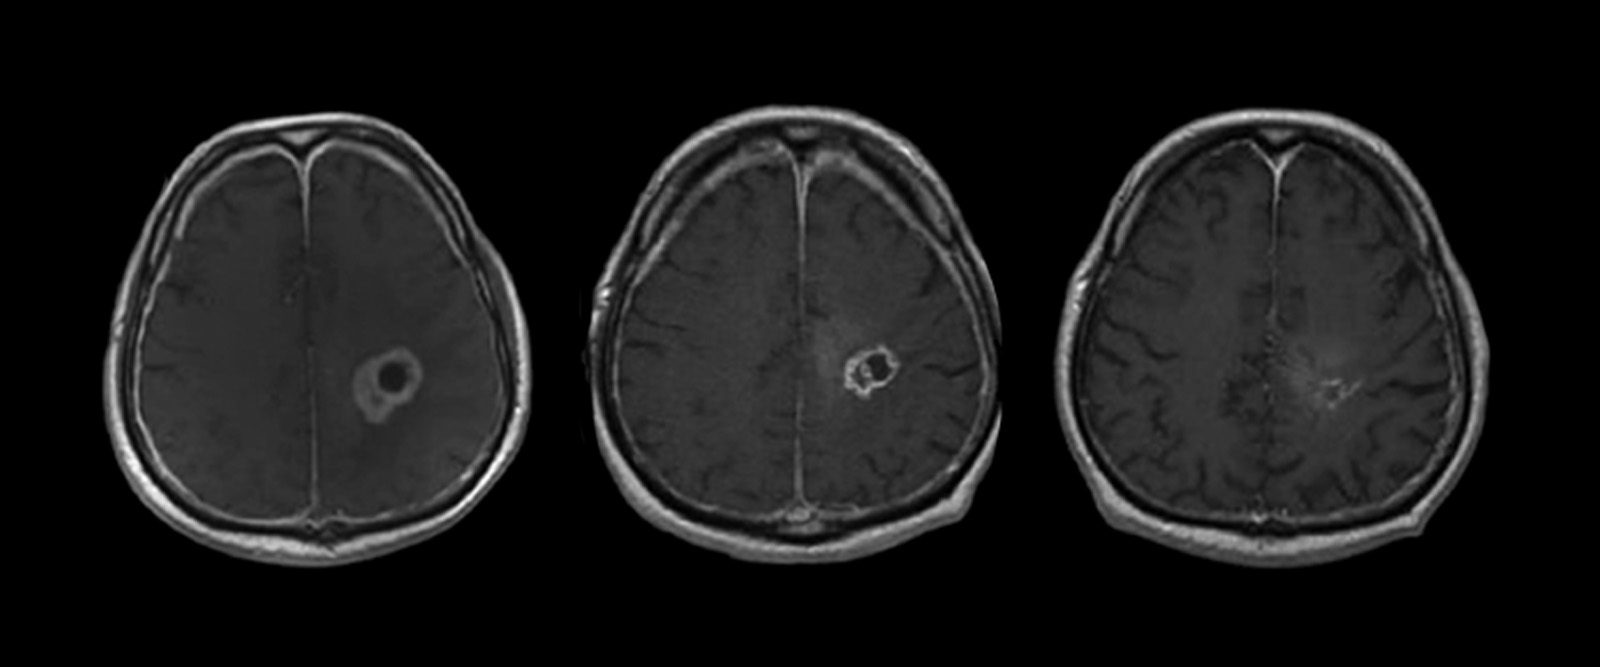

At the forefront of emerging technology, we provide access to pioneering clinical trials and advanced treatments, such as the Gamma Knife, stereotactic radio surgery, frameless stereotaxy, endoscopic surgery, and three-dimensional visualization in the operating room. The neurosurgery team at NewYork-Presbyterian Brooklyn Methodist Hospital is recognized for special expertise in treating brain tumors, collaborating with radiation oncologists to target cancerous tumor tissue with cutting-edge, minimally invasive techniques. Our surgeons are also experts in skull base surgery for pituitary tumors, chordomas, and other skull base tumors, which minimizes external incisions.